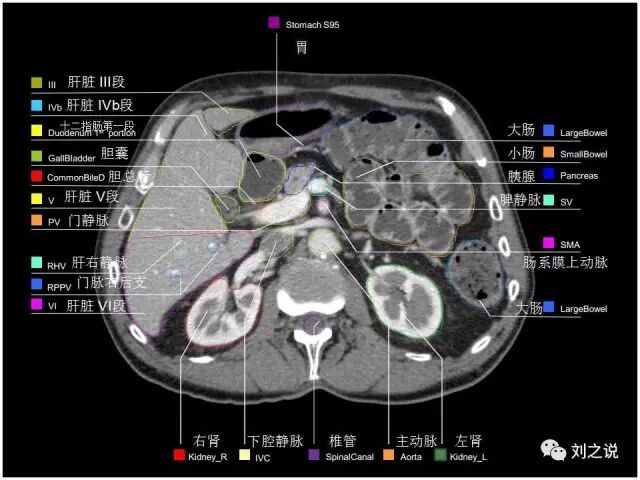

参考RTOG共识和3D-body解剖。

来源:刘之说